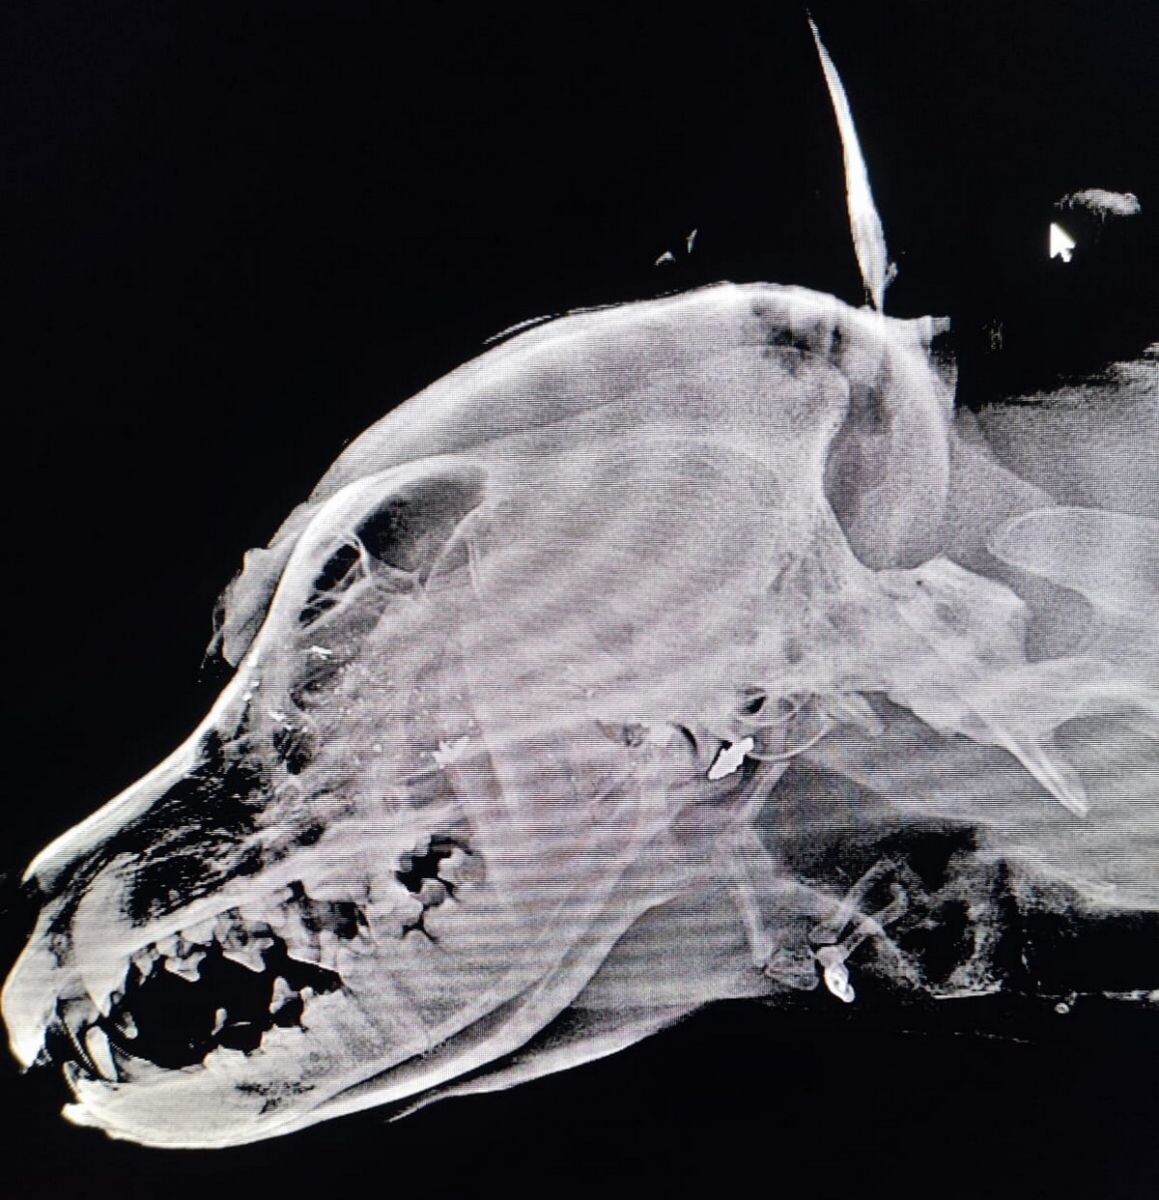

В Обнинске произошло чудо: добросердечные люди спасли жизнь хаски по имени Кевин, который пережил ужасный случай жестокости. По словам активистов, пес был найден с пулей в голове в поселке Вашутино. "Невозможно понять, как кто-то мог выстрелить в такую добрую и ласковую собаку. Он подошёл к людям за лаской, а в ответ получил пулю," – пишут в мини-приюте Harsh_eddie. Кевин несколько недель жил под строящимся домом, пока одна из местных жительниц не начала подкармливать его и даже оборудовала теплую будку. Но пес вновь исчез и вскоре был найден в Обнинске, тяжело раненым. Несмотря на серьезное ранение – пуля разлетелась на части, застряв в виске и в области гортани, – собака осталась жива. В клинике "Велес" Кевину провели обследования, выявив серьезные повреждения, включая заглоточный абсцесс, из-за которого ему больно есть. "Кевин невероятный, он всё понимает и доверяет людям, несмотря на боль," – отмечают спасатели. Для спасения жизни Кевина необходимы средства: на оплату ветеринарного

Кевин несколько недель жил под строящимся домом, пока одна из местных жительниц не начала подкармливать его и даже оборудовала теплую будку. Но пес вновь исчез и вскоре был найден в Обнинске, тяжело раненым. Несмотря на серьезное ранение – пуля разлетелась на части, застряв в виске и в области гортани, – собака осталась жива.

В клинике "Велес" Кевину провели обследования, выявив серьезные повреждения, включая заглоточный абсцесс, из-за которого ему больно есть.